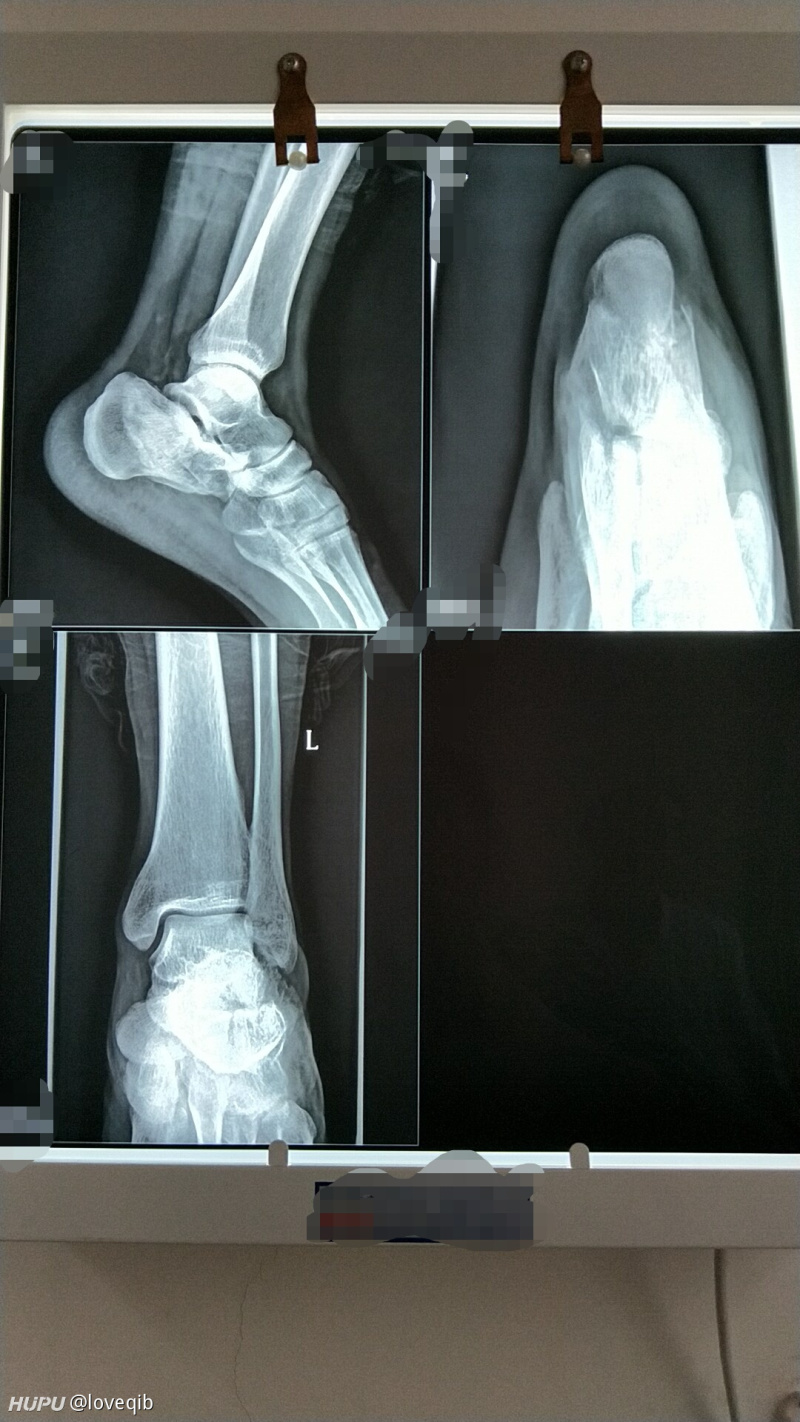

外踝及后踝骨折一例

图片尺寸612x816